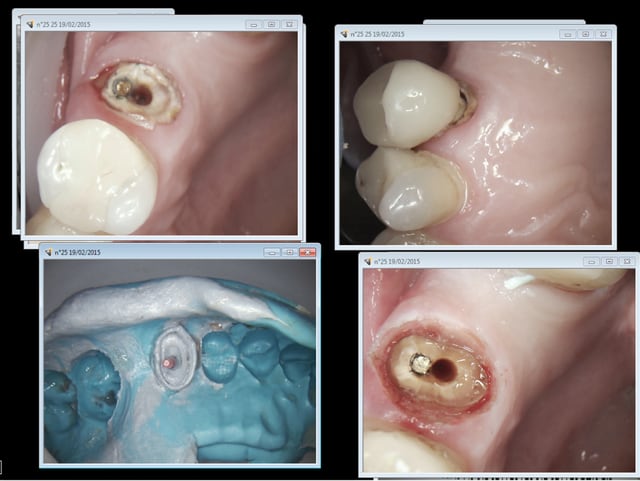

... un petit truc: maintien de l'Expasyl avec la provisoire.

H b atrice 15  1 rrqoux - Eugenol

H b atrice 15  3 rbtsjy - Eugenol

Marque a3 orange fyvhyq - Eugenol